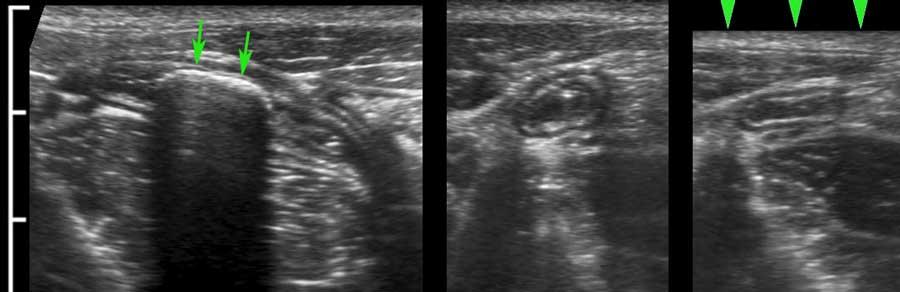

US fingerprint of the normal GI tract

Cấu trúc năm lớp kinh điển của thành ruột trên siêu âm được hiểu rõ nhất khi quan sát thành dạ dày chứa đầy dịch.

Các lớp, bắt đầu từ trong ra ngoài, có cấu trúc tăng âm-giảm âm-tăng âm-giảm âm-tăng âm hoặc trắng-đen-trắng-đen-trắng.

Cấu trúc thành ruột của Mỹ về cơ bản giống nhau từ dạ dày đến trực tràng.

Superficial mucosa

Lớp niêm mạc nông tăng âm rõ rệt, do chất nhầy và các hạt khí rất nhỏ bị giữ lại giữa các nhung mao ruột non.

Nó không thể nhận diện riêng biệt khi hòa lẫn với phân tăng âm, như trong hình ảnh siêu âm đại tràng này.

Lớp thanh mạc trắng bên ngoài chỉ có thể được xác định khi có cổ trướng.

Khi sử dụng đầu dò tần số cao, ba lớp giữa, bao gồm lớp niêm mạc sâu, lớp dưới niêm mạc và lớp cơ (đen-trắng-đen) luôn luôn hiển thị rõ ràng.

Ở bệnh nhân này với tình trạng ứ phân nặng, cấu trúc thành ba lớp chỉ có thể được nhận diện bằng đầu dò 12 MHz.